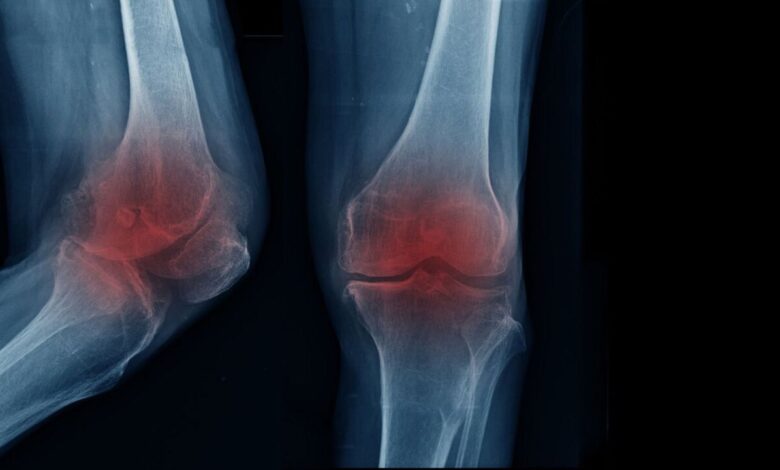

متخصص ارتوپدی و فلوشیپ جراحی زانو با بیان اینکه مفصل زانو یکی از فعال ترین اعضای بدن است و در طول زندگی فشار زیادی را تحمل می کند، تصریح کرد: با گذشت زمان و افزایش سن لایه غضروفی این مفصل به تدریج نازک و فرسوده می شود و این روند می تواند عامل آرتروز یا ساییدگی زانو باشد.

اکبری قدیمی ترین وی با بیان اینکه وقتی این غضروف عملکرد طبیعی خود را از دست می دهد، حرکت مفصل با سختی و درد و محدودیت حرکتی ظاهر می شود، ادامه داد: بروز آرتروز زانو همیشه به عامل خاصی محدود نمی شود و دلایل مختلفی در ایجاد آن نقش دارد.

این فوق تخصص ارتوپدی و فلوشیپ جراحی زانو با تاکید بر اینکه شایع ترین علامت آرتروز زانو درد زانو است که معمولا در مراحل اولیه هنگام راه رفتن یا انجام فعالیت ها بروز می کند، افزود: با پیشرفت تخریب غضروف، شدت درد افزایش می یابد و ممکن است فرد را حتی در حالت نشسته یا استراحت نیز آزار دهد.

اکبری قدیمی ترین وی با بیان اینکه علاوه بر درد، خشکی مفاصل به ویژه پس از بیدار شدن از خواب، کاهش دامنه حرکتی و دشواری در انجام حرکات روزانه از علائم شایع این بیماری است، افزود: اگرچه افزایش سن نقش مهمی در بروز آرتروز زانو دارد، اما سبک زندگی نیز در بروز آن نقش بسزایی دارد.